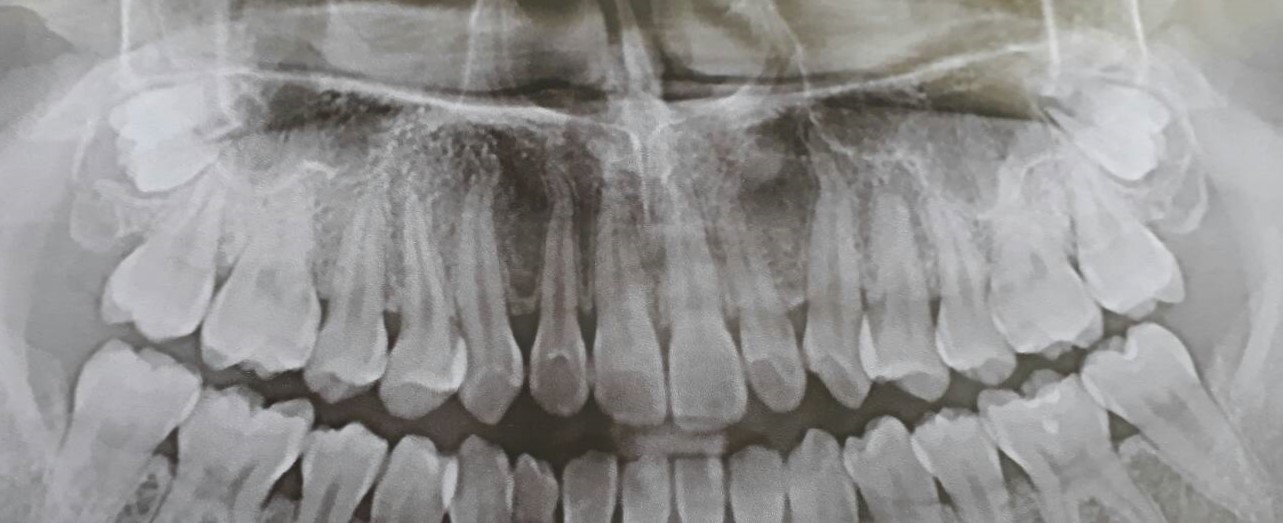

คือไปเอกซเรย์ฟันมาค่ะ มีฟันคุดสองซี่บน เหมือนไม่มีรากหรือมีนิดนึงอ่ะค่ะ คิดว่าจะไปถอนค่ะ แต่ไม่รู้ว่าจะเจ็บไหม

แล้วแบบนี้จะถอนยากไหมคะ คือจะได้ทำใจถูกค่ะว่าจะต้องจ่ายเท่าไหร่

ปล.ตอนนี้อายุ 20 แล้วค่ะ

หรือยังไม่ต้องถอนดีคะ ถ้าเก็บไว้จนรากงอกแล้วผ่าออกจะเจ็บไหมคะ

มีฟันคุดค่ะแต่ยังไม่มีรากถ้าถอนออกจะเจ็บไหมคะ